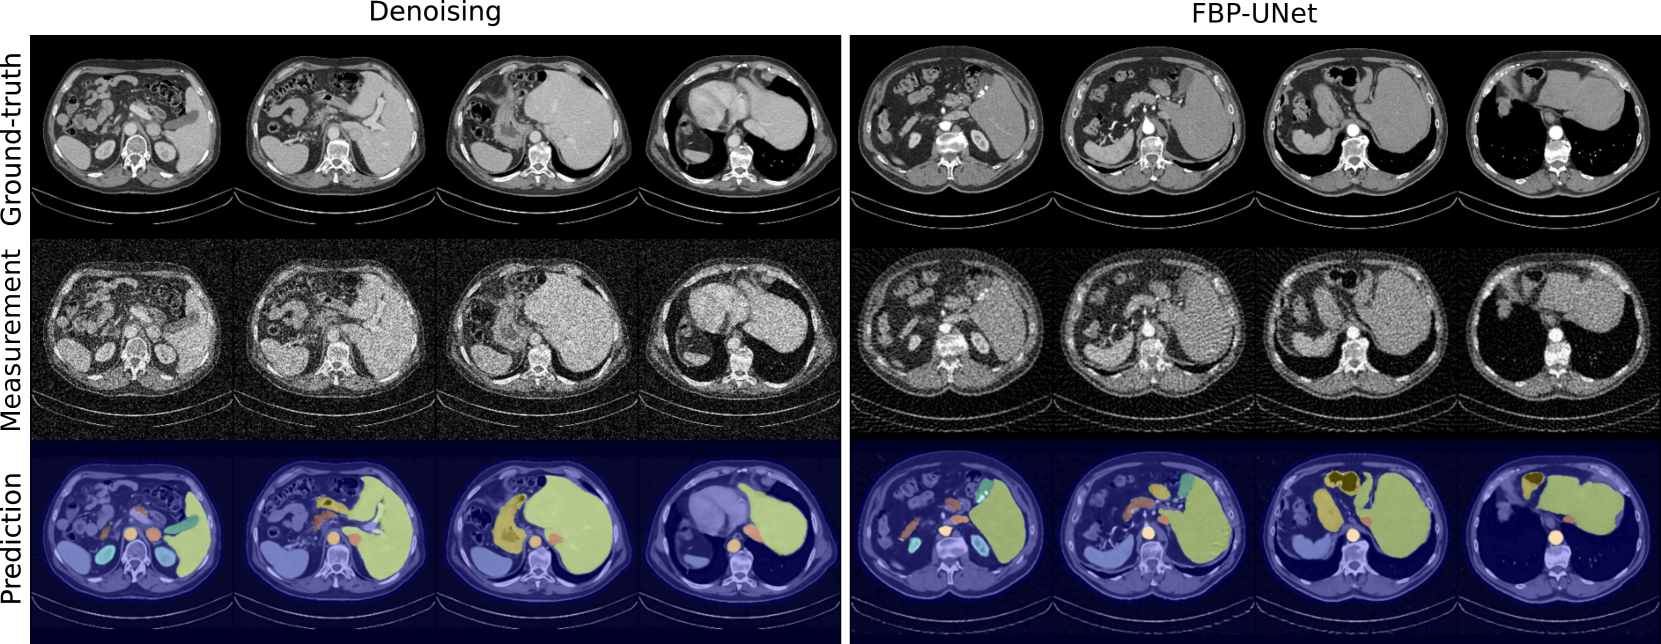

Refer to caption

(a) TotalSegmentator.

(b) FLARE23.

Figure 1: Example calibration data: ground-truth, measurement, and segmented predictions for both tasks and datasets.

Since sem-CRC𝑠𝑒𝑚-CRC{sem\text{-}{\text{CRC}}}italic_s italic_e italic_m - roman_CRC relies on a fixed segmentation model, we evaluate predictions in terms of mean structure-wise F1 score between the segmented outputs and the ground-truth annotations over 200 random volumes. For the TotalSegmentator dataset, we obtain 0.85±0.07plus-or-minus0.850.070.85\pm 0.070.85 ± 0.07 and 0.83±0.08plus-or-minus0.830.080.83\pm 0.080.83 ± 0.08 for denoising and FBP-UNet, respectively; and, equivalently, 0.88±0.06plus-or-minus0.880.060.88\pm 0.060.88 ± 0.06 and 0.87±0.07plus-or-minus0.870.070.87\pm 0.070.87 ± 0.07 for the FLARE23 dataset. Although we see a slight drop in performance compared to the metrics reported in [17], these results confirm predictions are of reasonable quality for segmentation, and we include some examples in Fig. 1.